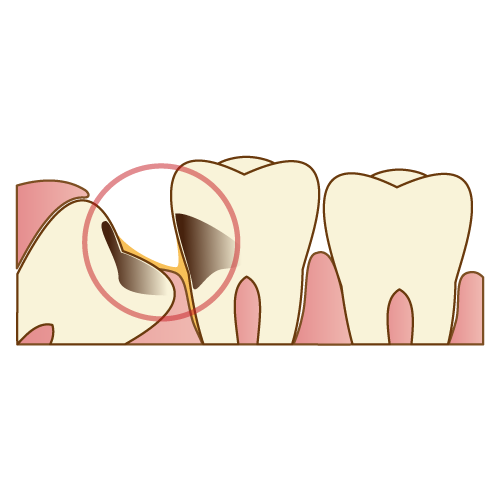

こちらは健康な歯の構造です。外側からエナメル質。象牙質。神経。の三層構造です。

エナメル質は人体で一番硬い部分で、虫歯の進行はゆっくりです。象牙質に虫歯が入り込むと大きく広がり、進行が早くなります。神経に近付くと痛みを感じるようになり、神経を取る治療になる可能性が高くなります。

こちらは虫歯になります。虫歯はレントゲンだと黒く写ってきます。虫歯の好発部位は、歯の隣接面(接触してる部分)、咬合面(噛む面)。ここを中心に見て虫歯のチェックをします。